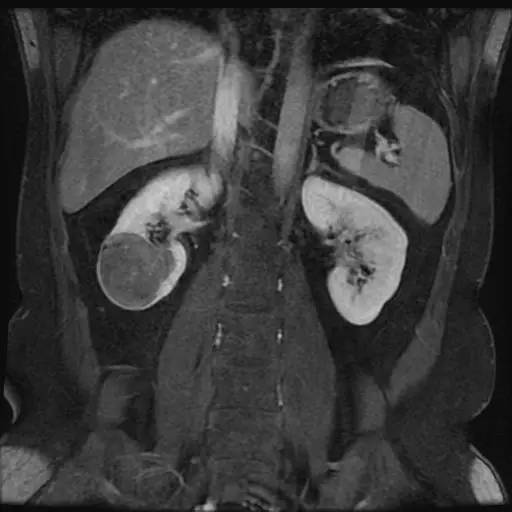

右肾中下部见类圆形约52*49*59毫米类圆形短和稍长T1、短和长T2异常信号肿块,可见假包膜,DWI呈晕环结节状稍高和稍低信号,反相位图像病变信号未见异常减低;皮质期病变未见异常强化,髓质期及延迟期持续轻度强化;病变内小部分区域未见强化。所见肝胆、胰腺、脾脏及双侧肾上腺未见异常,肝门、肾门及所见腹膜后未见异常肿大淋巴结影。

影像诊断:右肾中下部少血供肿块伴出血、坏死和囊变,考虑:恶性肿瘤,以肾癌(非透明细胞癌)可能性最大,不能完全除外表现不典型的血管平滑肌脂肪瘤。